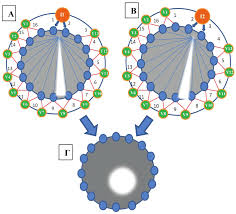

Η αρχή της τομογραφίας εμπέδησης βασίζεται στον υπολογισμό και στις μεταβολές της σύνθετης αντίστασης του ανθρώπινου σώματος σε μια εγκάρσια διατομή, η οποία μετράται με τη βοήθεια 16 ηλεκτροδίων. Τα ηλεκτρόδια είναι τοποθετημένα γύρω από το επίπεδο της εγκάρσιας διατομής που πρόκειται να μελετηθεί, ενώ η ανασύνθεση της εικόνας αναπαράγεται σε monitor το οποίο διαθέτει ο τομογράφος. Όταν εφαρμόζεται εναλλασσόμενο ρεύμα γνωστής έντασης μεταξύ δύο ηλεκτροδίων δημιουργείται ηλεκτρική δραστηριότητα μεταξύ τους.

Η ηλεκτρική αυτή δραστηριότητα καταγράφεται ως διαφορά δυναμικού από τα υπόλοιπα 13 ζεύγη ηλεκτροδίων τα οποία κατανέμονται κυκλοτερώς στην επιφάνεια της νοητής διατομής που μελετάται. Έτσι, σχηματίζεται εναλλασσόμενο ηλεκτρικό πεδίο, οι δυναμικές γραμμές του οποίου διαπερνούν εγκάρσια το μελετώμενο ανατομικό τμήμα. Κάθε φορά που οι δυναμικές γραμμές του εναλλασσόμενου ηλεκτρικού πεδίου διέρχονται από μια περιοχή η οποία δεν είναι συμπαγής, αυτή εκλαμβάνεται ως περιοχή μεγάλης αντίστασης και απεικονίζεται από τον τομογράφο με λευκό χρώμα.

Στη συνέχεια από τις μετρήσεις αυτές είναι δυνατός ο υπολογισμός των τιμών των ηλεκτρικών αντιστάσεων εντός του εξεταζόμενου οργάνου με την τεχνική της οπισθοπροβολής (backprojection), ενώ με τη βοήθεια ειδικού προγράμματος του ηλεκτρονικού υπολογιστή καθίσταται δυνατή η δημιουργία εικόνας, που είναι εικόνα κατανομής της αγωγιμότητας. Ο υπολογιστικός ανασυνδυασμός των 208 διαφορετικών διαφορών δυναμικού που προκύπτουν, μετά και την εφαρμογή ειδικών φίλτρων, συνθέτει μια εικόνα 32×32 εικονοστοιχείων τα οποία οπτικοποιούν τις μεταβολές της σύνθετης αντίστασης της μελετώμενης περιοχής. Μάλιστα, επειδή η ειδική αγωγιμότητα εξαρτάται από την συχνότητα, για κάθε εφαρμογή ηλεκτρικού ρεύματος συγκεκριμένης συχνότητας προκύπτει και διαφορετική εικόνα της κατανομής της ηλεκτρικής αγωγιμότητας, γεγονός που αξιοποιούν οι ειδικοί για την λήψη πολλών διαφορετικών εικόνων με εφαρμογή διαφορετικών συχνοτήτων ρεύματος.

Η αρχή της τομογραφίας εμπέδησης βασίζεται στον υπολογισμό και στις μεταβολές της σύνθετης αντίστασης του ανθρώπινου σώματος σε μια εγκάρσια διατομή, η οποία μετράται με τη βοήθεια 16 ηλεκτροδίων. Τα ηλεκτρόδια είναι τοποθετημένα γύρω από το επίπεδο της εγκάρσιας διατομής που πρόκειται να μελετηθεί, ενώ η ανασύνθεση της εικόνας αναπαράγεται σε monitor το οποίο διαθέτει ο τομογράφος. Όταν εφαρμόζεται εναλλασσόμενο ρεύμα γνωστής έντασης μεταξύ δύο ηλεκτροδίων δημιουργείται ηλεκτρική δραστηριότητα μεταξύ τους.

Η ηλεκτρική αυτή δραστηριότητα καταγράφεται ως διαφορά δυναμικού από τα υπόλοιπα 13 ζεύγη ηλεκτροδίων τα οποία κατανέμονται κυκλοτερώς στην επιφάνεια της νοητής διατομής που μελετάται. Έτσι, σχηματίζεται εναλλασσόμενο ηλεκτρικό πεδίο, οι δυναμικές γραμμές του οποίου διαπερνούν εγκάρσια το μελετώμενο ανατομικό τμήμα. Κάθε φορά που οι δυναμικές γραμμές του εναλλασσόμενου ηλεκτρικού πεδίου διέρχονται από μια περιοχή η οποία δεν είναι συμπαγής, αυτή εκλαμβάνεται ως περιοχή μεγάλης αντίστασης και απεικονίζεται από τον τομογράφο με λευκό χρώμα.

Στη συνέχεια από τις μετρήσεις αυτές είναι δυνατός ο υπολογισμός των τιμών των ηλεκτρικών αντιστάσεων εντός του εξεταζόμενου οργάνου με την τεχνική της οπισθοπροβολής (backprojection), ενώ με τη βοήθεια ειδικού προγράμματος του ηλεκτρονικού υπολογιστή καθίσταται δυνατή η δημιουργία εικόνας, που είναι εικόνα κατανομής της αγωγιμότητας. Ο υπολογιστικός ανασυνδυασμός των 208 διαφορετικών διαφορών δυναμικού που προκύπτουν, μετά και την εφαρμογή ειδικών φίλτρων, συνθέτει μια εικόνα 32×32 εικονοστοιχείων τα οποία οπτικοποιούν τις μεταβολές της σύνθετης αντίστασης της μελετώμενης περιοχής. Μάλιστα, επειδή η ειδική αγωγιμότητα εξαρτάται από την συχνότητα, για κάθε εφαρμογή ηλεκτρικού ρεύματος συγκεκριμένης συχνότητας προκύπτει και διαφορετική εικόνα της κατανομής της ηλεκτρικής αγωγιμότητας, γεγονός που αξιοποιούν οι ειδικοί για την λήψη πολλών διαφορετικών εικόνων με εφαρμογή διαφορετικών συχνοτήτων ρεύματος.